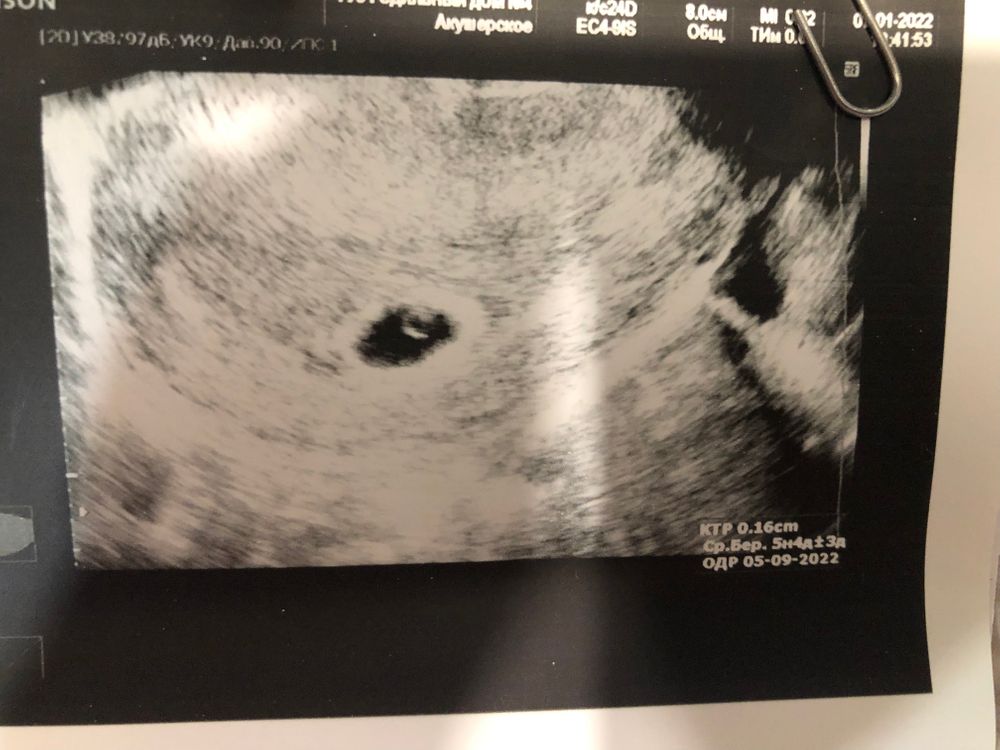

В итоге, все в пределах нормы, плодное яйцо с эмбриончиком нашли, отслойки нет. Сердцебиения ещё не видно, будем искать через неделю.

Размеры:

ПЯ- 11,6мм

ЖМ- 3,0мм

КТР- 1,6 мм